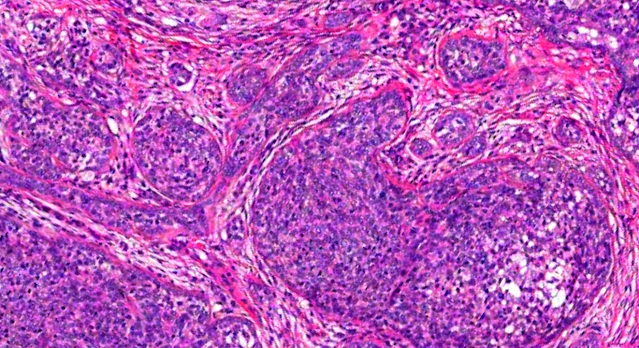

Dermatopathology Case 212 Get link Facebook X Pinterest Email Other Apps May 12, 2022 Small, non-ulcerated nodule on the face of a 45 year old male. Answer Get link Facebook X Pinterest Email Other Apps Comments